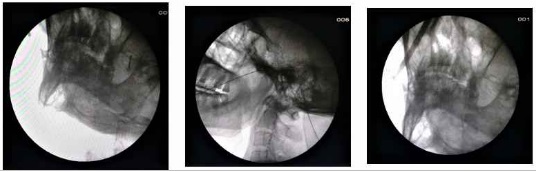

Η θερμοπηξία με ραδιοσυχνότητες (RFTC) είναι μια από τις πιο αποτελεσματικές και ασφαλείς θεραπευτικές πράξεις ημερήσιας νοσηλείας. Γίνεται στο χειρουργείο υπό ακτινοσκοπική καθοδήγηση με τοπική αναισθησία και ήπια καταστολή. Προσφέρει 80 έως 90% ανακούφιση από τον πόνο, έχοντας ωστόσο ορισμένα μειονεκτήματα όπως, παράπονα του ασθενούς για μούδιασμα ή ασυνήθιστη αίσθηση στην περιοχή κατανομής του νεύρου στο πρόσωπο. Με τη μέθοδο αυτή μια βελόνα εισάγεται στο ωοειδές τρήμα στη βάση του κρανίου και μέσω αυτής εισέρχεται το ηλεκτρόδιο που χορηγεί την ενέργεια και καυτηριάζει το γάγγλιο του τρίδυμου νεύρου.